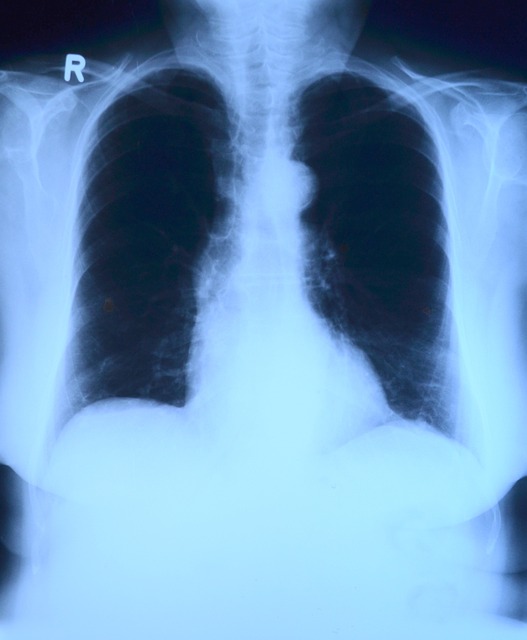

정기적인 건강 검진을 통해 심장이나 폐 관련 질환을 조기에 발견하고 관리하는 것이 중요합니다.